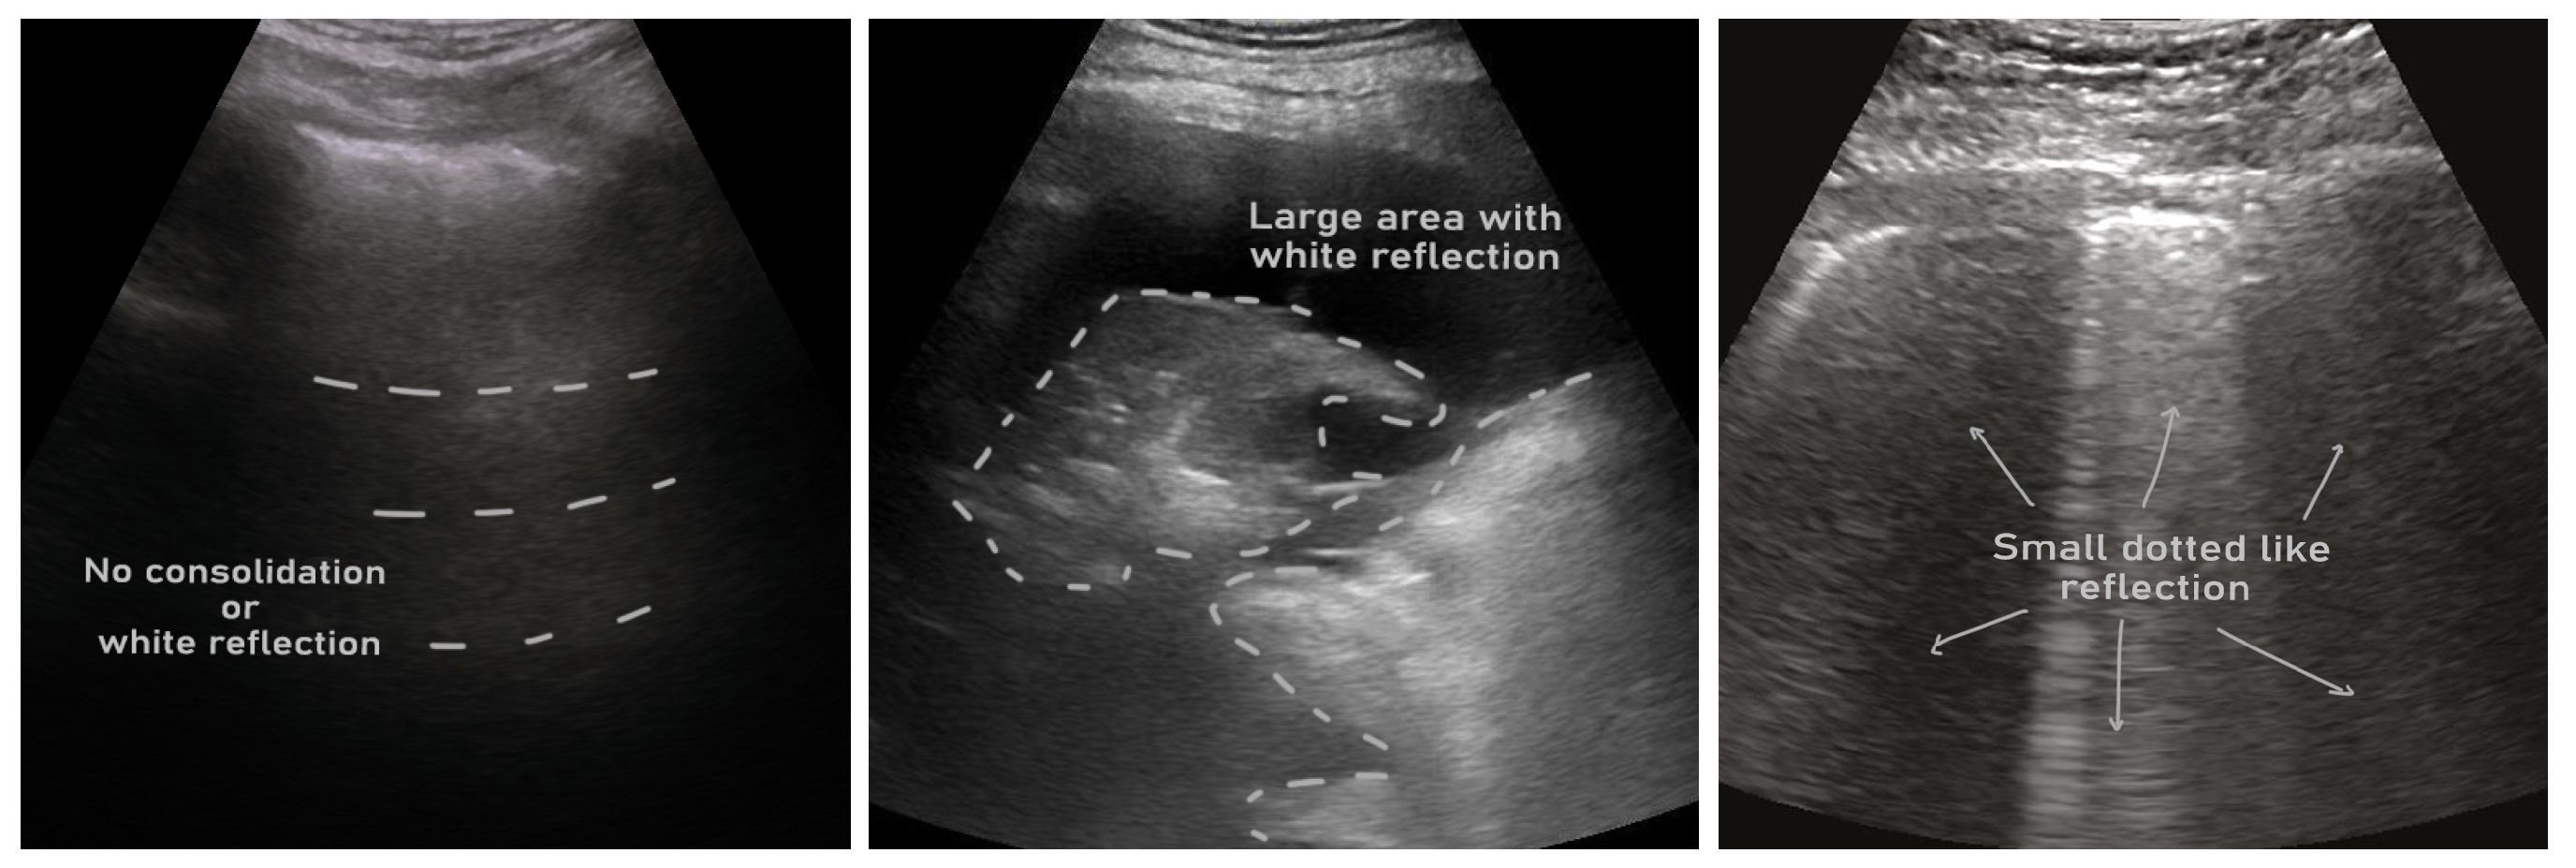

- ICLUS-DB: Soldati et al. [24] published an internationally standardized lung ultrasound acquisition protocol along with a four-level scoring scheme in March 2020. This dataset contains 277 ultrasound videos (consisting of 58,924 frames) of 17 confirmed COVID-19, 4 suspected COVID-19, and 14 healthy subjects. These data were collected at various clinical centers in Italy using various ultrasound scanners by either linear or convex probes. To evaluate the progress of pathology, this data consortium defined a four-level scoring system ranging from 0 to 3. Continuous pleural-line and horizontal A-lines indicate a healthy lung with a score of 0. Score 1 is tagged for initial abnormality when alterations in the pleural line appear. Score 2 is more severe than 1 and is associated with small consolidations in the lung. Score 3 is the most severe grade, which is associated with the presence of a larger hyperechogenic area below the pleural surface (i.e., white lung).